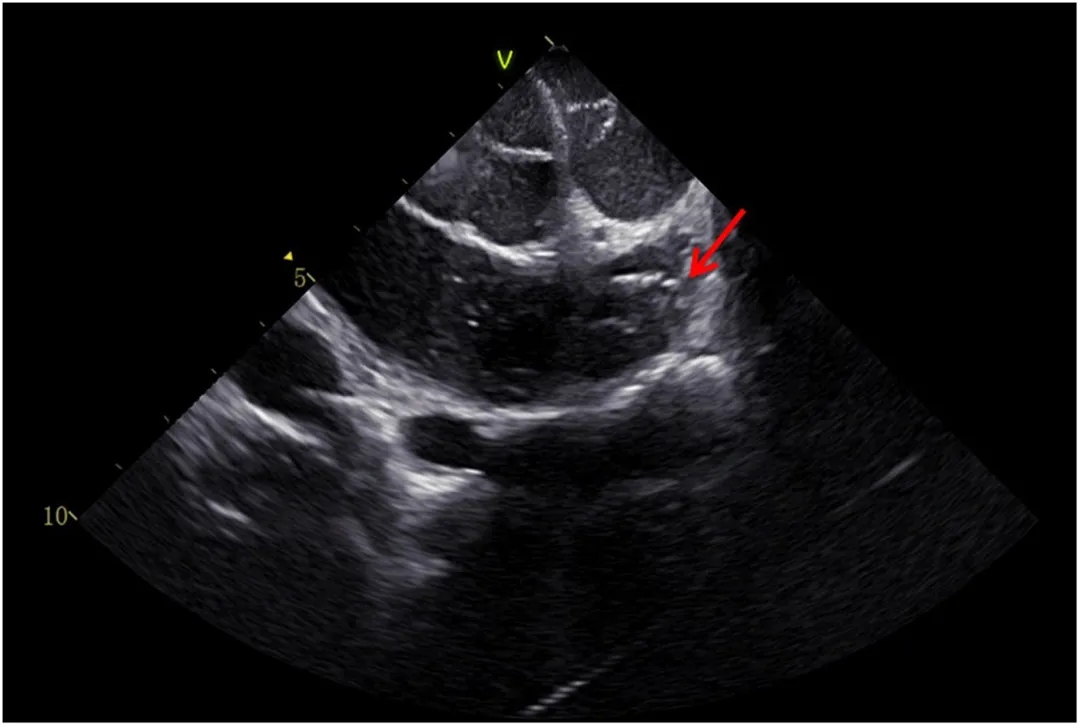

患者于我院全身麻醉下行心内电生理检查,明确房速起源位于左心耳尖端(图2),心动周期约480 ms。导管头端位置经心腔内超声(图3)确认。

图3 心腔内超声图像显示,消融导管头端位于左心耳尖端邻近区域。